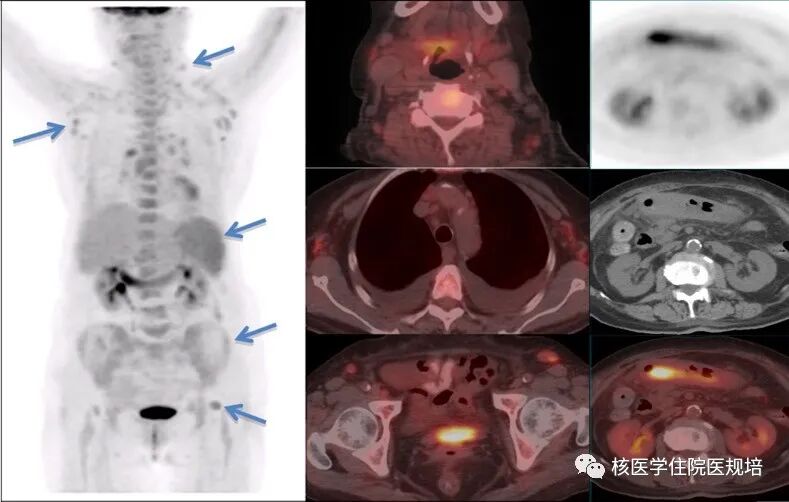

患者为53岁男性,7年前因晕厥查holter提示窦性停搏1-3s”,行永久型起搏器植入;2个月前患者出现发热伴寒战,体温最高39.5℃,门诊予抗感染治疗效果不佳;1周前入院行经食道超声心动检查发现右心房导线上赘生物形成,临床疑诊起搏器植入相关感染。进一步行FDG PET/CT显像以明确诊断(图1,图2)。

18F-FDG PET/CT显像结果示:胸壁囊袋区域可见高密度植入装置影,周围区域未见明显异常FDG摄取;右心房、右心室可见沿肌壁走行分布的弥漫性放射性浓聚;导线走行区域亦可见点状放射性浓聚影(SUVmax2.6);左肺内见多发模糊斑片影、实变影及索条影,呈不同程度FDG摄取增高表现(SUVmax分布在3.14.6),同时见左侧胸腔少量积液;左肺门可见多发FDG摄取增高的淋巴结影(SUVmax3.6),呈长椭圆形,短径分布在0.50.8cm。脾脏FDG摄取略高于肝脏(SUVmax2.7),富含红骨髓区域骨骼亦呈FDG摄取弥漫性增高(SUVmax3.3),平扫CT均未见明确异常结构改变。扫描野内其他脏器组织未见异常FDG摄取或结构改变。

起搏器植入术后,右心房室及导线走行区FDG代谢增高灶考虑感染性心内膜炎;左肺内多发感染,左侧胸腔积液,肺门淋巴结反应性增生;脾脏及骨髓FDG代谢弥漫增高,考虑血行感染所致可能性大,建议进一步病原学检查。

本例起搏器植入后并发感染性心内膜炎的患者在FDG PET/CT上显示出其特征性影像表现,即见沿左、右心房和右心室肌壁走行分布的弥漫性FDG高摄取,但部分患者可表现不均匀性或局灶性放射性浓聚[4],这种异常摄取为局部炎性细胞摄取显像剂所致,反映感染性心内膜炎的病理特性,而正常状态下通常是看不到心房摄取的。此外,超声心动所发现的赘生物若摄取FDG也是感染性心内膜性的表现,但阳性率较低,可能与病灶体积、心脏舒缩运动及设备分辨率影响有关。对于起搏器置入术后出现长期发热的患者,若发现上述任何一种异常表现时,均应考虑存在感染性心内膜炎。值得注意的是,尽管PET显像中一般看不到心房对FDG的摄取,但由于心肌对FDG的高摄取时可能使心房的异常摄取被忽略,因此采用抑制心脏生理性摄取的技术手段可能有助于感染病灶的检出,如检查前食用高脂低碳水化合物饮食。